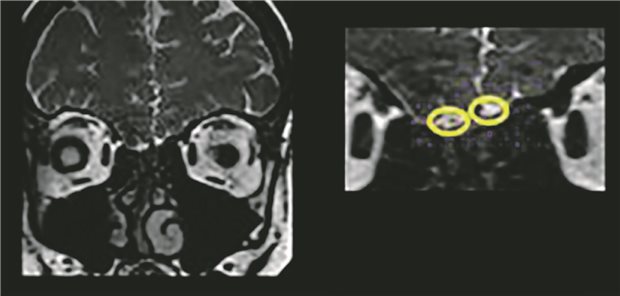

Havanna-Syndrom: Keine Anzeichen für Hirnschäden im MRT

Es zeigte sich in der Gesamtschau das bei Patienten mit einer COVID-Impfung sowohl für die Akutphase nach einer Infektion mit SARS-CoV-2, definiert als die ersten 30 Tage, als auch für postakute Zeitfenster, ein (in vielen Fällen signifikant) geringeres Risiko für Herzinsuffizienz, venöse Thromboembolien und arterielle thromboembolische Ereignisse inklusive Koronarereignisse besteht.